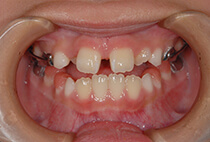

5歳6ヶ月、受け口が気になるとお母様と一緒にご来院。

「幼稚園の間に治療スタートしたい」「小学校入学時には装置に慣れた状態でいたい」とのご希望で、矯正治療をスタートしました。

治療は、急速拡大+前方けん引装置から。

3ヶ月で骨格バランスが大きく改善し、1年3ヶ月後にはさらにバランスの整ったお顔立ちへ。

成長に合わせて3回の急速拡大を行い、夜間のマウスピースとお口の機能訓練で成長をサポート。小学生を正常なバランスで過ごすことができました。

中学校入学と同時にマウスピースを卒業し、今後は予防管理へ移行予定です。

「早めに始めてよかった」と喜んでいらっしゃいます。

5歳6ヶ月、受け口が気になり、お母様と一緒にご来院。

治療は、急速拡大+前方牽引装置から。

1ヶ月で骨格バランスが大きく改善しました。

小学1年生の7ヶ月後には、さらにバランスの整った噛み合わせに。

成長に合わせて3回の急速拡大を行い、夜間のマウスピースとお口の機能訓練で成長をサポート。

小学生を正常なバランスで過ごすことができました。